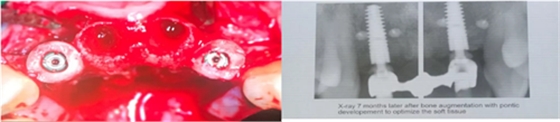

該患者的中切牙需要拔除,而雙側(cè)側(cè)切牙的骨寬度和骨高度均不足,應(yīng)該如何處理?由此,教授提出了骨環(huán)植骨技術(shù)。

依據(jù)病例的遠(yuǎn)期隨訪觀察,教授認(rèn)為骨環(huán)技術(shù)可以長期穩(wěn)定地維持種植體周圍的骨高度,制備骨環(huán)的材料可以取自患者的自體骨,也可以應(yīng)用骨替代材料。

1. 骨環(huán)技術(shù)在垂直骨增量的術(shù)式中是一項(xiàng)可靠的,結(jié)果可預(yù)期的手術(shù)方法。

2. 骨替代材料制作的骨環(huán)在行垂直骨增量的患者中,術(shù)后8個(gè)月能夠形成良好的骨愈合。